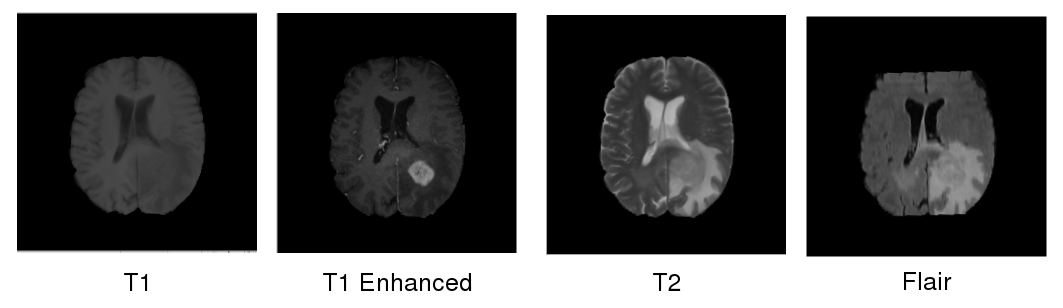

Whereas earlier methods mainly aim to capture 3 dimensional structure of the anatomy using a single modality, the MRI devices provide different image contrasts with different gray scale intensities. For instance, in the BRATS dataset[10], for each patient four different modality images such as T1-weighted MRI, T1-weighted enhanced MRI, T2-weighted MRI and FLAIR are acquired. As can be seen in Figure 1 all of these modalities provide different information about the brain anatomy of the patient. However, in the recent works, these modalities are generally just concatenated, and fed to CNNs as an input. Thus, the CNNs learn a single representation for all modalities. In this work, we adapt a number of fusion methods that were previously applied on video action recognition [4] problem for learning separate representations for each modality, and we combine these modalities efficiently in the CNN framework for an improved tumor segmentation. Our experiments show that with appropriate fusion method and fusion point in the CNN architecture, the error rate of the CNNs could be reduced by 30%.

Refer to caption

Figure 1: Different modalities for a sample patient data from BRATS dataset [10]. Each modality provides different information that complement each other.